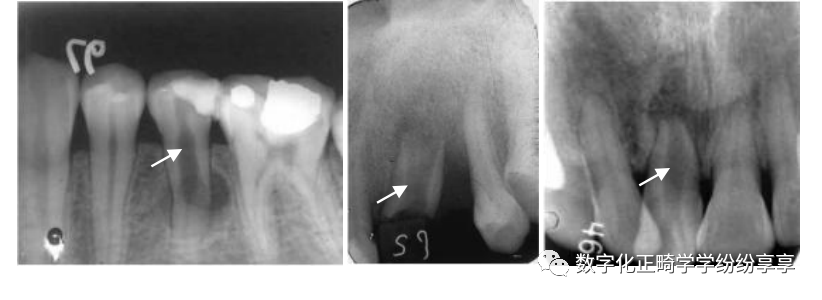

(3) 骨质改变:(可追加薛氏位片或MRI)

髁突硬化

曲面断层片怎么看正畸【曲面断层片(全景片)】如何解读和查看:牙周?牙体?牙髓?关节?_https://www.jmylbn.com_新闻资讯_第27张

髁突经咽侧位片示髁突前斜面密质骨不规则增生硬化

髁突前斜面模糊不清

曲面断层片怎么看正畸【曲面断层片(全景片)】如何解读和查看:牙周?牙体?牙髓?关节?_https://www.jmylbn.com_新闻资讯_第28张

髁突经咽侧位片示髁突前斜面密质骨致密影像消失,边缘模糊粗糙

髁突小凹陷缺损

曲面断层片怎么看正畸【曲面断层片(全景片)】如何解读和查看:牙周?牙体?牙髓?关节?_https://www.jmylbn.com_新闻资讯_第29张

髁突经咽侧位片示髁突前斜面骨质呈小的凹陷状缺损,周围骨质密度减低

髁突前斜面广泛破坏

曲面断层片怎么看正畸【曲面断层片(全景片)】如何解读和查看:牙周?牙体?牙髓?关节?_https://www.jmylbn.com_新闻资讯_第30张

髁突经咽侧位片示髁突前斜面密质骨边缘消失,表面不整齐,有较广泛的骨质侵蚀及破坏

髁突磨平、变短小

曲面断层片怎么看正畸【曲面断层片(全景片)】如何解读和查看:牙周?牙体?牙髓?关节?_https://www.jmylbn.com_新闻资讯_第31张

髁突骨质增生

曲面断层片怎么看正畸【曲面断层片(全景片)】如何解读和查看:牙周?牙体?牙髓?关节?_https://www.jmylbn.com_新闻资讯_第32张